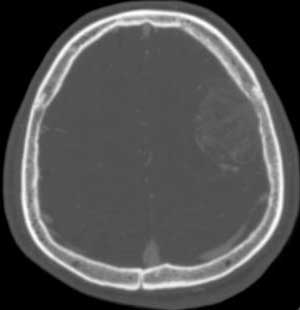

男,35岁。言语不清10余天,口角歪斜。

左颞部稍低密度d形肿块影阴,密度不均,内有不规则囊变区,局部脑白质受压塌陷,肿块周围少许水肿带,中线轻度右移位,增强扫描明显强化,局部颅板有轻微侵蚀,如此大的肿块中线结构移位不明显说明肿块位于脑外,如此强化的脑外肿瘤只有一个------脑膜瘤

由图可见,左侧颞部有占位病变,使的中线受压移位。局部脑白质受压塌陷,可考滤是肿瘤。再跟具发病部位,我觉得恶性肿瘤的可能性大 。

与颅骨广基相连,不均匀强化,脑白质受压,考虑脑外肿瘤,脑膜瘤。

平扫呈低密度,与颅内板接触广泛,脑皮层受压内移,增强明显强化,内示不规则的坏死区,周围脑实质内未见明显水肿.

脑膜瘤.

定位:脑灰白质界面内移,肿瘤位于脑外,应该明确。

定性:支持脑膜瘤。

本例我首先考虑脑膜瘤,但其具有形态不规则、密度不均匀、有明显的坏死液化、没有完整和明显的包膜、且呈明显不均匀性强化等诸多恶性特点,应该首先考虑恶性脑膜瘤(但颅骨只有轻微受压而没有明显的受浸润破坏现象也不太支持)。

还有不支持的地方,比如那么大地肿瘤而瘤周水肿不明显。所以,我第2考虑海绵状血管瘤。建议mri检查。

左侧颞顶叶见d形肿块灶,密度不均,其内可见低密度影,局部脑白质所压移位,病灶明显强化。支持脑膜瘤